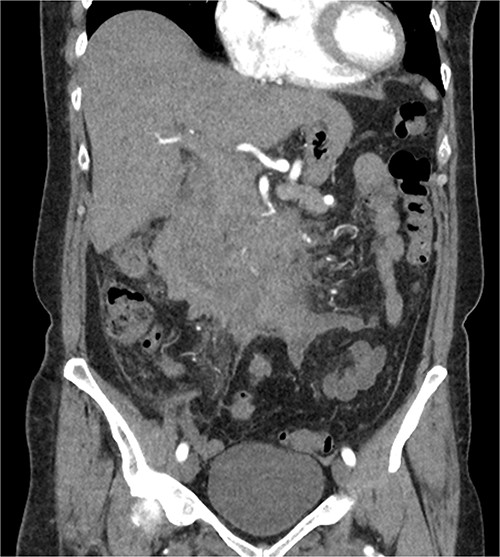

The radiologist suggested a computer tomography (CT) scan to further explore the potential causes for this fluid. The CT abdomen and pelvis revealed extensive oedema and induration surrounding the duodenum with a complex hyperdense fluid, extending from this site to the paracolic gutters and into the pelvis. While these findings are suspicious of a paraduodenal hemorrhage from a ruptured duodenal ulcer and hemoperitoneum, they were not typical for perforated duodenal ulcer or erosion into the blood vessels. Differentials were an infiltrating mass either fibrotic or of a lymphoproliferative origin. However, this could not explain the complex fluid in the abdomen (Figs 1 and 2).

CT abdomen, coronal view. Hyperdense fluid centered around the duodenum and tracking into the paracolic gutters. Appearance concerning for paraduodenal hemorrhage, infiltrating mass was considered less likely.